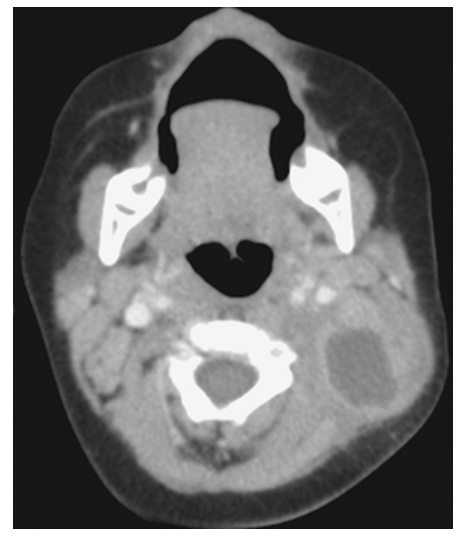

What does the figure show?

Brachial Cleft Cyst. Axial CECT in a child shows a cystic lesion in the left posterior neck with overlying infiltration of the fat representing an inflamed second BCC.